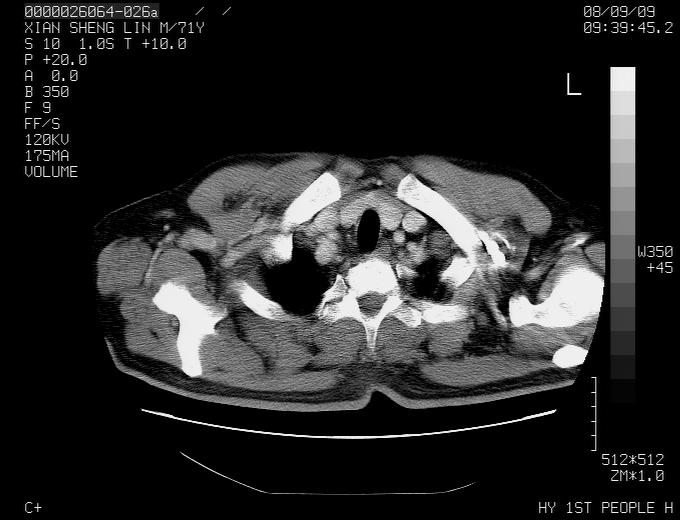

标题: CT15869:男性,71岁,因咳嗽而就诊,请讨论右上肺病变性质 [打印本页]

患者,男性,71岁,因咳嗽而就诊,

典型的右肺中心性肺癌并纵隔淋巴结转移

右肺中心性肺癌并纵隔淋巴结转移可能性大!

1,右肺中心型ca,气管隆突旁淋巴结转移。

2,右膈明显抬高,建议肝脏扫描排除转移或原发灶。